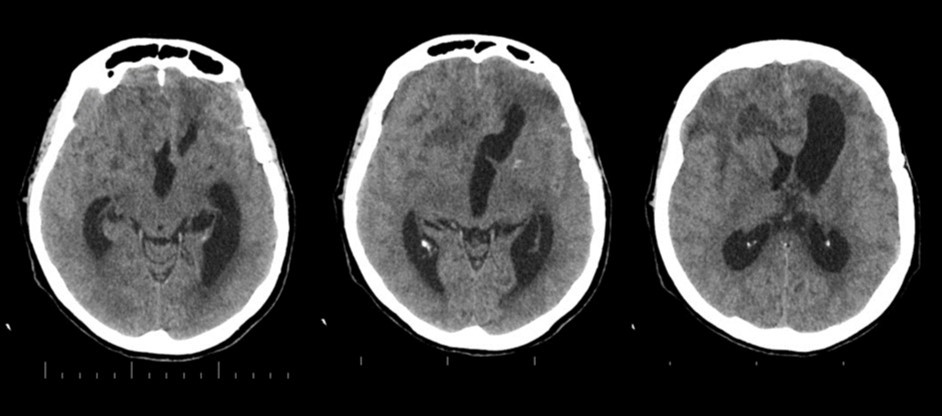

A 65 years-old woman with no relevant medical history was carried to the emergency department of another institution for the sudden onset of headache and vomiting, followed by loss of consciousness. She underwent a cerebral CT scan, that showed diffuse SAH in the basal cisterns and anterior interemispheric fissure (Figure 1). The CT angiogram displayed a single aneurysm of the anterior communicating artery, that local radiologists considered unfavorable for endovascular treatment. The patient was therefore surgically managed, with left pterional craniotomy for aneurysm clipping and right external ventricular drain (EVD) positioning. In the following days the woman reacquired alertness; the EVD was removed without need of permanent shunting and she was transferred to rehabilitation four weeks after the operation in quite good conditions.

Figure 1.Non-contrast axial CT scan showing thick subarachnoid hemorrhage in the basal cisterns and in the frontal interemispheric space